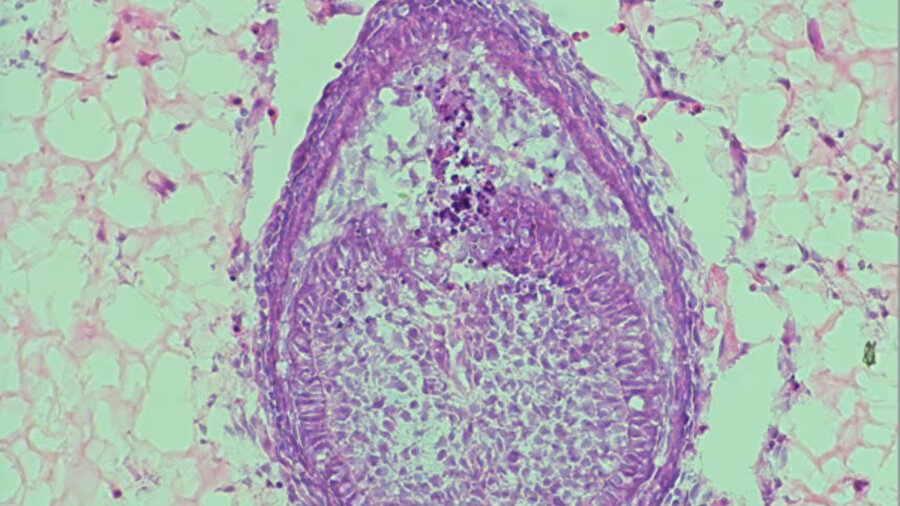

2013 yılında yapılan çalışmada dişlerin büyümesi için kolajen adlı bir protein kullanılırken, yeni çalışmada su oranı yüksek bir jel (hidrojel) kullanılıyor. Hücreler bir araya getiriliyor, bu jelin içine yerleştiriliyor ve yaklaşık sekiz gün boyunca büyümeye bırakılıyor. Bu süreç sonunda dişe benzer yapılar oluşuyor.